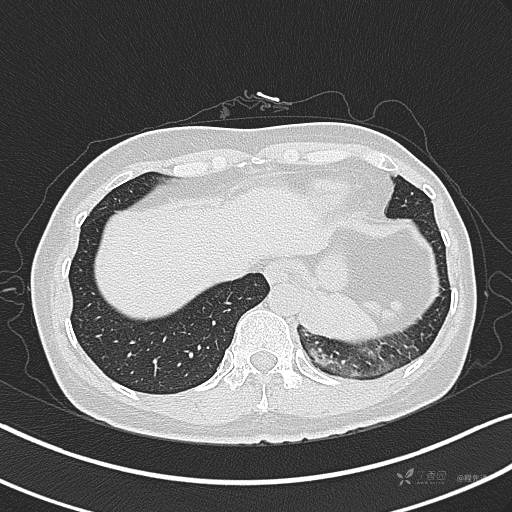

增强动脉期

动脉期CT值约74HU